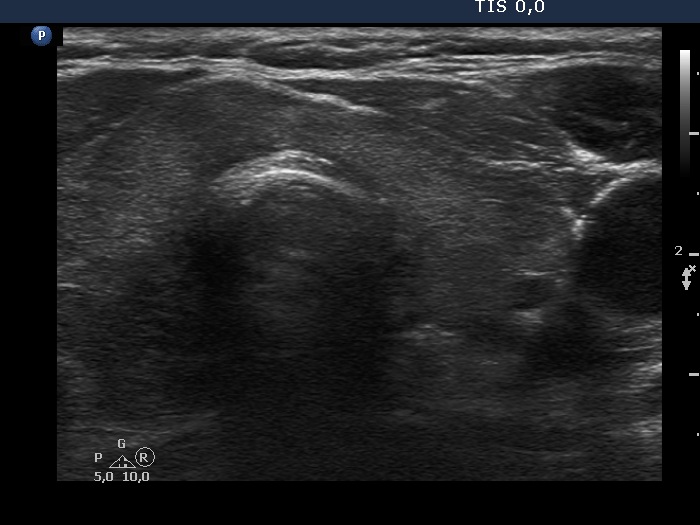

Patient referred for evaluation of thyroid nodule - final diagnosis Hashimoto's thyroiditis - Case 25.

Follow-up investigation two years after the first visit (ultrasonographic picture 4)

Left lobe, horizontal scan. The pattern is similar to that seen at first examination.